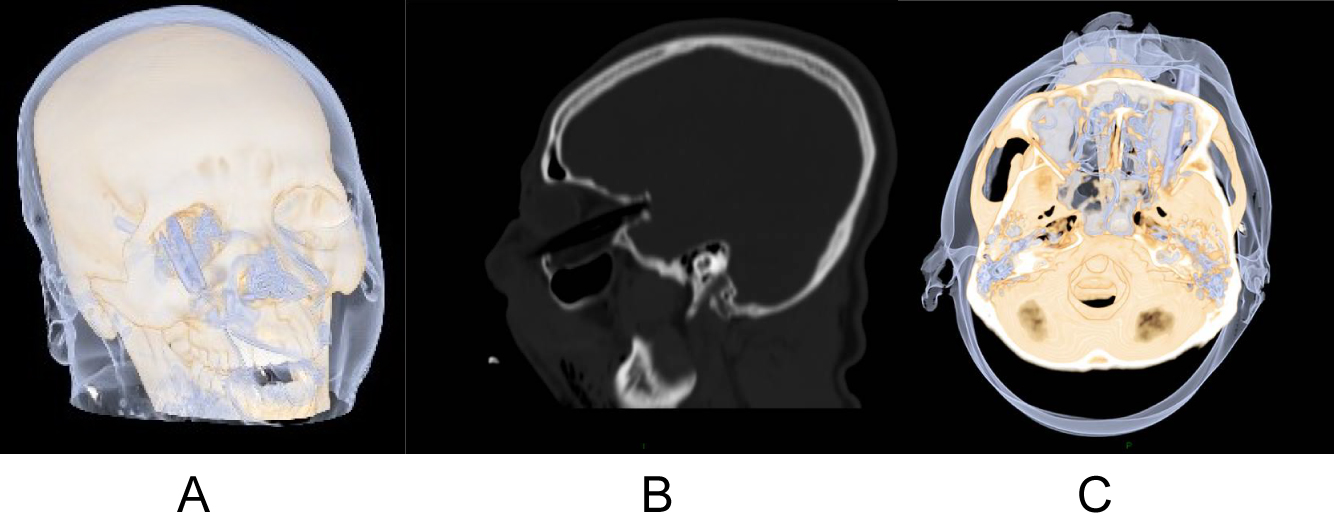

A 25-year-old man was admitted to the emergency room with multi trauma injuries after falling from a second-floor balcony into his neighbor's garden. On arrival, the patient was sedated and placed under artificial respiration. On physical examination, the only external evidence of injury was a 1.5 cm wooden foreign body protruding from the upper lip (Figure 1). Closer examination revealed the foreign body inside the cheek without penetrating the oral cavity. Computed tomography (CT) of the head and face were performed. The images depicted a well formed, radiolucent area with a density similar to that of air in the right orbit. This was later identified as a foreign body penetrating the right orbit in an axial plane from inferior to superior direction. It deflected the globe and penetrated the orbital apex towards the middle cranial fossa to the point of touching but not penetrating the dura mater (Figure 2). A fracture in the floor of the right orbit without the involvement of the lower orbital rim was revealed (Figure 3). Herniation of the inferior Rectus muscle and fat from the orbit into the right maxillary sinus cavity were present (Figure 4). Ocular examination showed no injuries to the globe. The patient received tetanus toxoid and prophylactic intravenous wide spectrum antibiotics. The patient underwent an emergency operation, in the presence of an ophthalmologist and a neurosurgeon. The approach was extra-oral with the aim of exploring and removing the foreign body. The intra-orbital foreign body proved to be a 9 cm bamboo stick (Figure 5). The bamboo stick was meticulously removed. There was no leakage of cerebrospinal fluid (CSF) and no brain tissue was found during exploration examination of the foreign body after its removal. Immediate postoperatively, the patient was transferred to the intensive care. Follow up CT scan demonstrated intact right globe, optic nerve and dura mater. There were no radiolucent findings suggesting that no foreign body remnants were present.

Figure 2: (A, B, C) 3D CT scan demonstrating a foreign body mimicking air in the orbit, deflected the globe and penetrated the orbital apex towards the middle cranial fossa to the point of touching but not penetrating the dura mater. View Figure 2